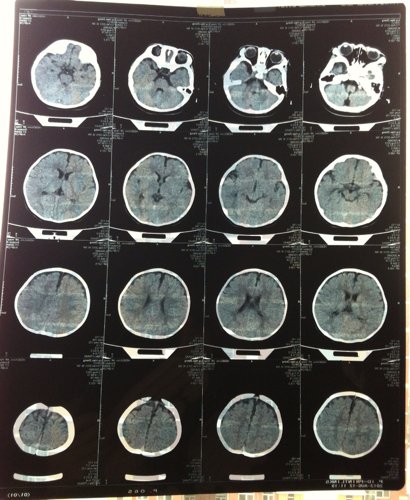

婴儿脑积水 孩子六个多月了,有一天头往一边摇和蹭脖子一样,眼睛有点向上翻,能用声音打断,去医院做 了动态脑电图和CT,脑电图没异常,CT显示:双侧额部颅板下可见窄条形水样密度,与脑组织分界清晰,脑实质内未见异常密度,脑沟、裂、池无增宽,脑室系统无扩张,中线结构居中。诊断意见:考虑轻度外部性脑积水。医生开了:小儿盐酸赖氨酸颗粒。 由于早产35+6出生三天 CT显示低密度影,医生说能吸收就没治疗。请问这病严重吗,需要住院治疗吗,从一侧摇头可能会变成癫痫吗,他睡觉时拇指有点往里扣,抓东西、玩手时都能伸开,有的时候他还会攥着小拳头发出狠声,还有六个月20斤不会站在大人腿上跳,其他该会的会了,这都正常吗?麻烦您了 点击展开 匿名用户 2013-08-16 15:44 为您推荐: 其他回答 你好,这只是轻度的脑发育欠佳而不是脑积水,在治疗上只需要使用营养脑细胞的药物和高压氧治疗就可以了。通常会在1周岁左右恢复正常的。 不倒翁52 2013-08-16 16:01 相关问题 宝宝四十多天,今天用手敲打了他的头感觉像熟透的西瓜样声音会不会是脑积水 小孩才44天!检查有脑积水?可能是因难产,脑内有出血的症状?头部稍显大!有一个眼睛总有眼屎?要怎样治 婴儿脑积水 脖子骨骼力度不够怎么办 两个月左右的

了动态脑电图和CT,脑电图没异常,CT显示:双侧额部颅板下可见窄条形水样密度,与脑组织分界清晰,脑实质内未见异常密度,脑沟、裂、池无增宽,脑室系统无扩张,中线结构居中。诊断意见:考虑轻度外部性脑积水。医生开了:小儿盐酸赖氨酸颗粒。 由于早产35+6出生三天 CT显示低密度影,医生说能吸收就没治疗。请问这病严重吗,需要住院治疗吗,从一侧摇头可能会变成癫痫吗,他睡觉时拇指有点往里扣,抓东西、玩手时都能伸开,有的时候他还会攥着小拳头发出狠声,还有六个月20斤不会站在大人腿上跳,其他该会的会了,这都正常吗?麻烦您了